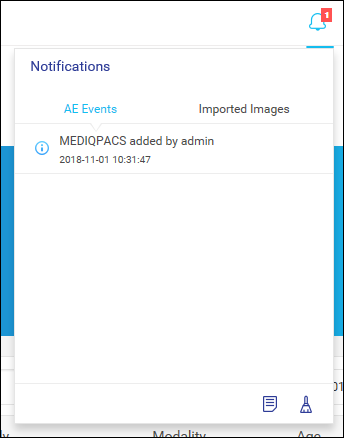

通知

用户可以在 MediQPACS 中管理通知。